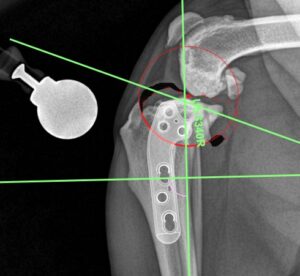

TPLO Pre Op plan